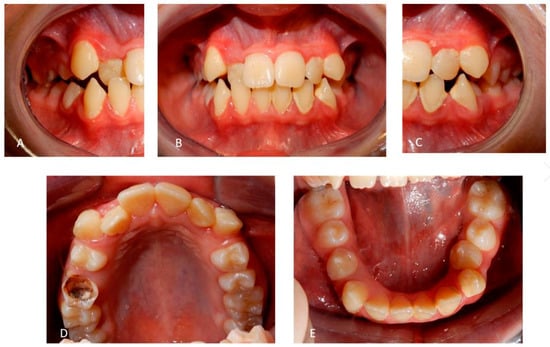

2. Case Presentation

2.1. Patient A

2.2. Patient B

2.3. Father